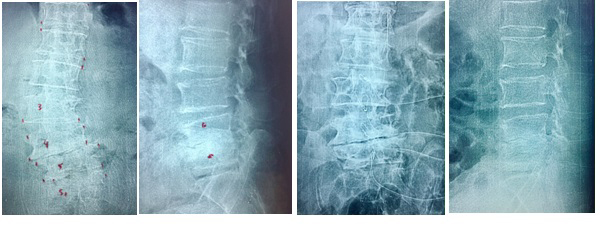

| Gambar 4. Sebelum PSLD dan Sesudah PSLD, Pasien usia 61 tahun |